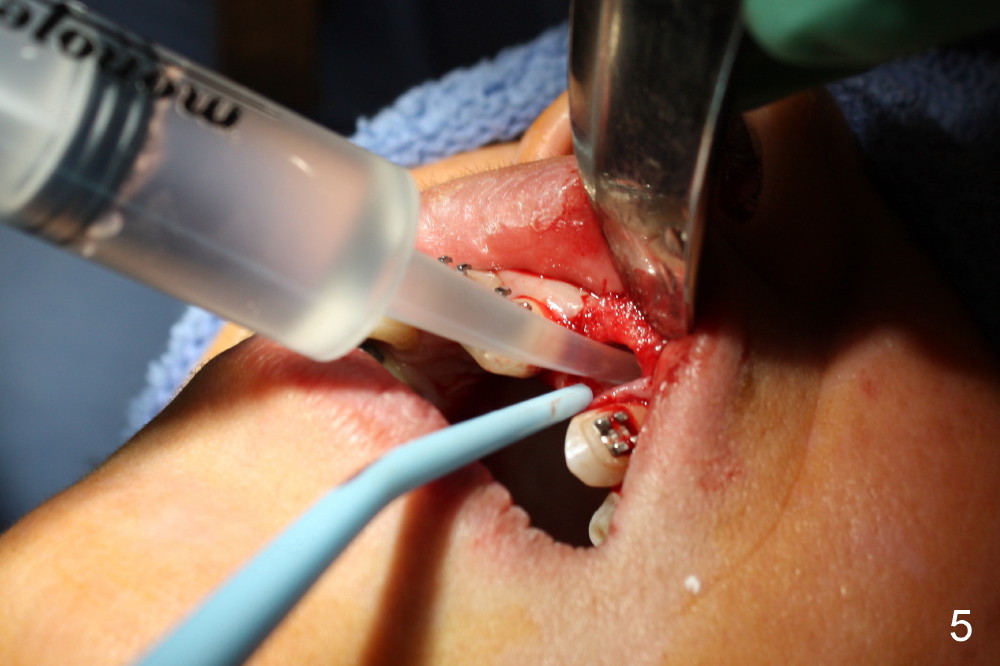

A 56-year-old Oriental lady is going to have immediate implant for the upper left lateral incisor after lengthened preparation (1 2 3 4). There is an indistinct fistula (Fig.1 <) and purulent discharge on anesthetic injection (Fig.2 <). The residual root is exposed (Fig.3 *) following a trapezoidal incision (arrowheads). After tooth extraction and socket debridement with a serrated curette (Fig.4), copious irrigation is conducted with a large monojet and normal saline (Fig.5). The socket will be soaked with non-woven gauze saturated with Clindamycin (Fig.6). The advantage of this antibiotic over Amoxicillin is that there is less mess with the former (completely dissolves). But Clindamycin is bitter. This amalgam well is saved to keep autogenous bone from the reamer and mix with allograft if needed.